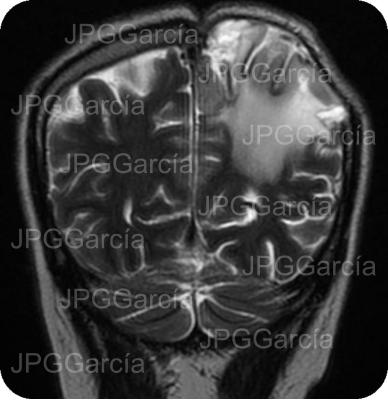

Tumor del plano esfenoidal clasificado por imagen como Meningioma visto a través de resonancia magnética cortes axial y coronal